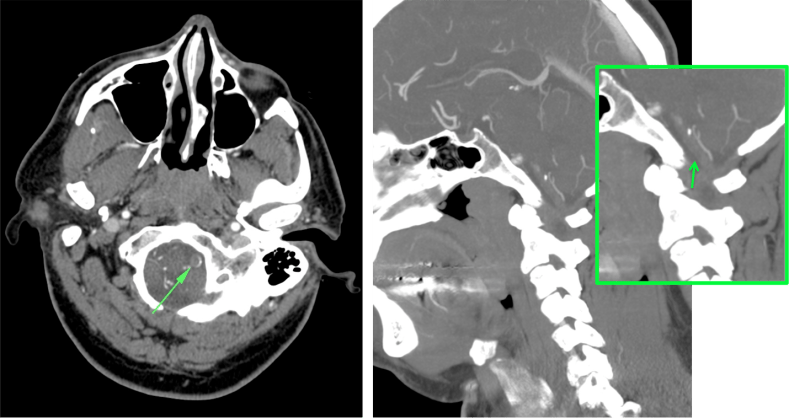

ANGIOGRAFÍA TC.

Sirve para:

- Definir el lugar de oclusión.

- Descartar disección arterial.

- Grado de colateralidad.

- Grado de arterioesclerosis.

Con la información aportada podremos pronosticar mejor la localización y extensión del infarto. Además, proporciona un mapa vascular para el tratamiento endovascular.

La angioTC nos sirve para:

- Detectar trombosis: informar acerca de la apariencia, localización, dimensiones. Localizaciones frecuentes:

- Tándem ACI-ACMedia

- Tronco Basilar

- Región carotídea.

- Segmento M1 de ACM

- Segmento M2 de ACM

- Detectar disección arterial (produce ictus por suelta de embolos o por oculisón hemodinámica)